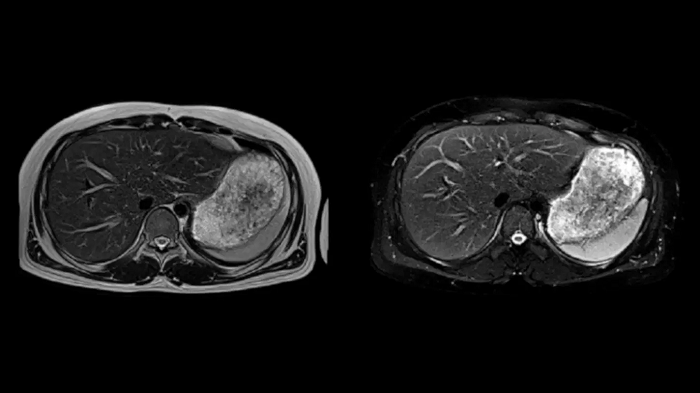

Abdomen

T1 VIBE Dixon with CAIPIRINHA

Get benefitted from Siemens Healthineers dedicated CAIPIRINHA acceleration to gain a complete abdominal volume within a single breath-hold. The Dixon technique offers outstanding fat water separation for a flawless representation of the abdominal anatomy.

MAC-ID: 7aaaa0165.

MAC-ID: 7aaaa0165. Image Credit: Siemens Healthineers

Body diffusion imaging

For all-inclusive abdominal MR capabilities, outstanding quality diffusion imaging.

T2 BLADE

T2 motion insensitive abdominal imaging with BLADE results in outstanding outcomes, regardless of the orientation or if fat saturation is needed.